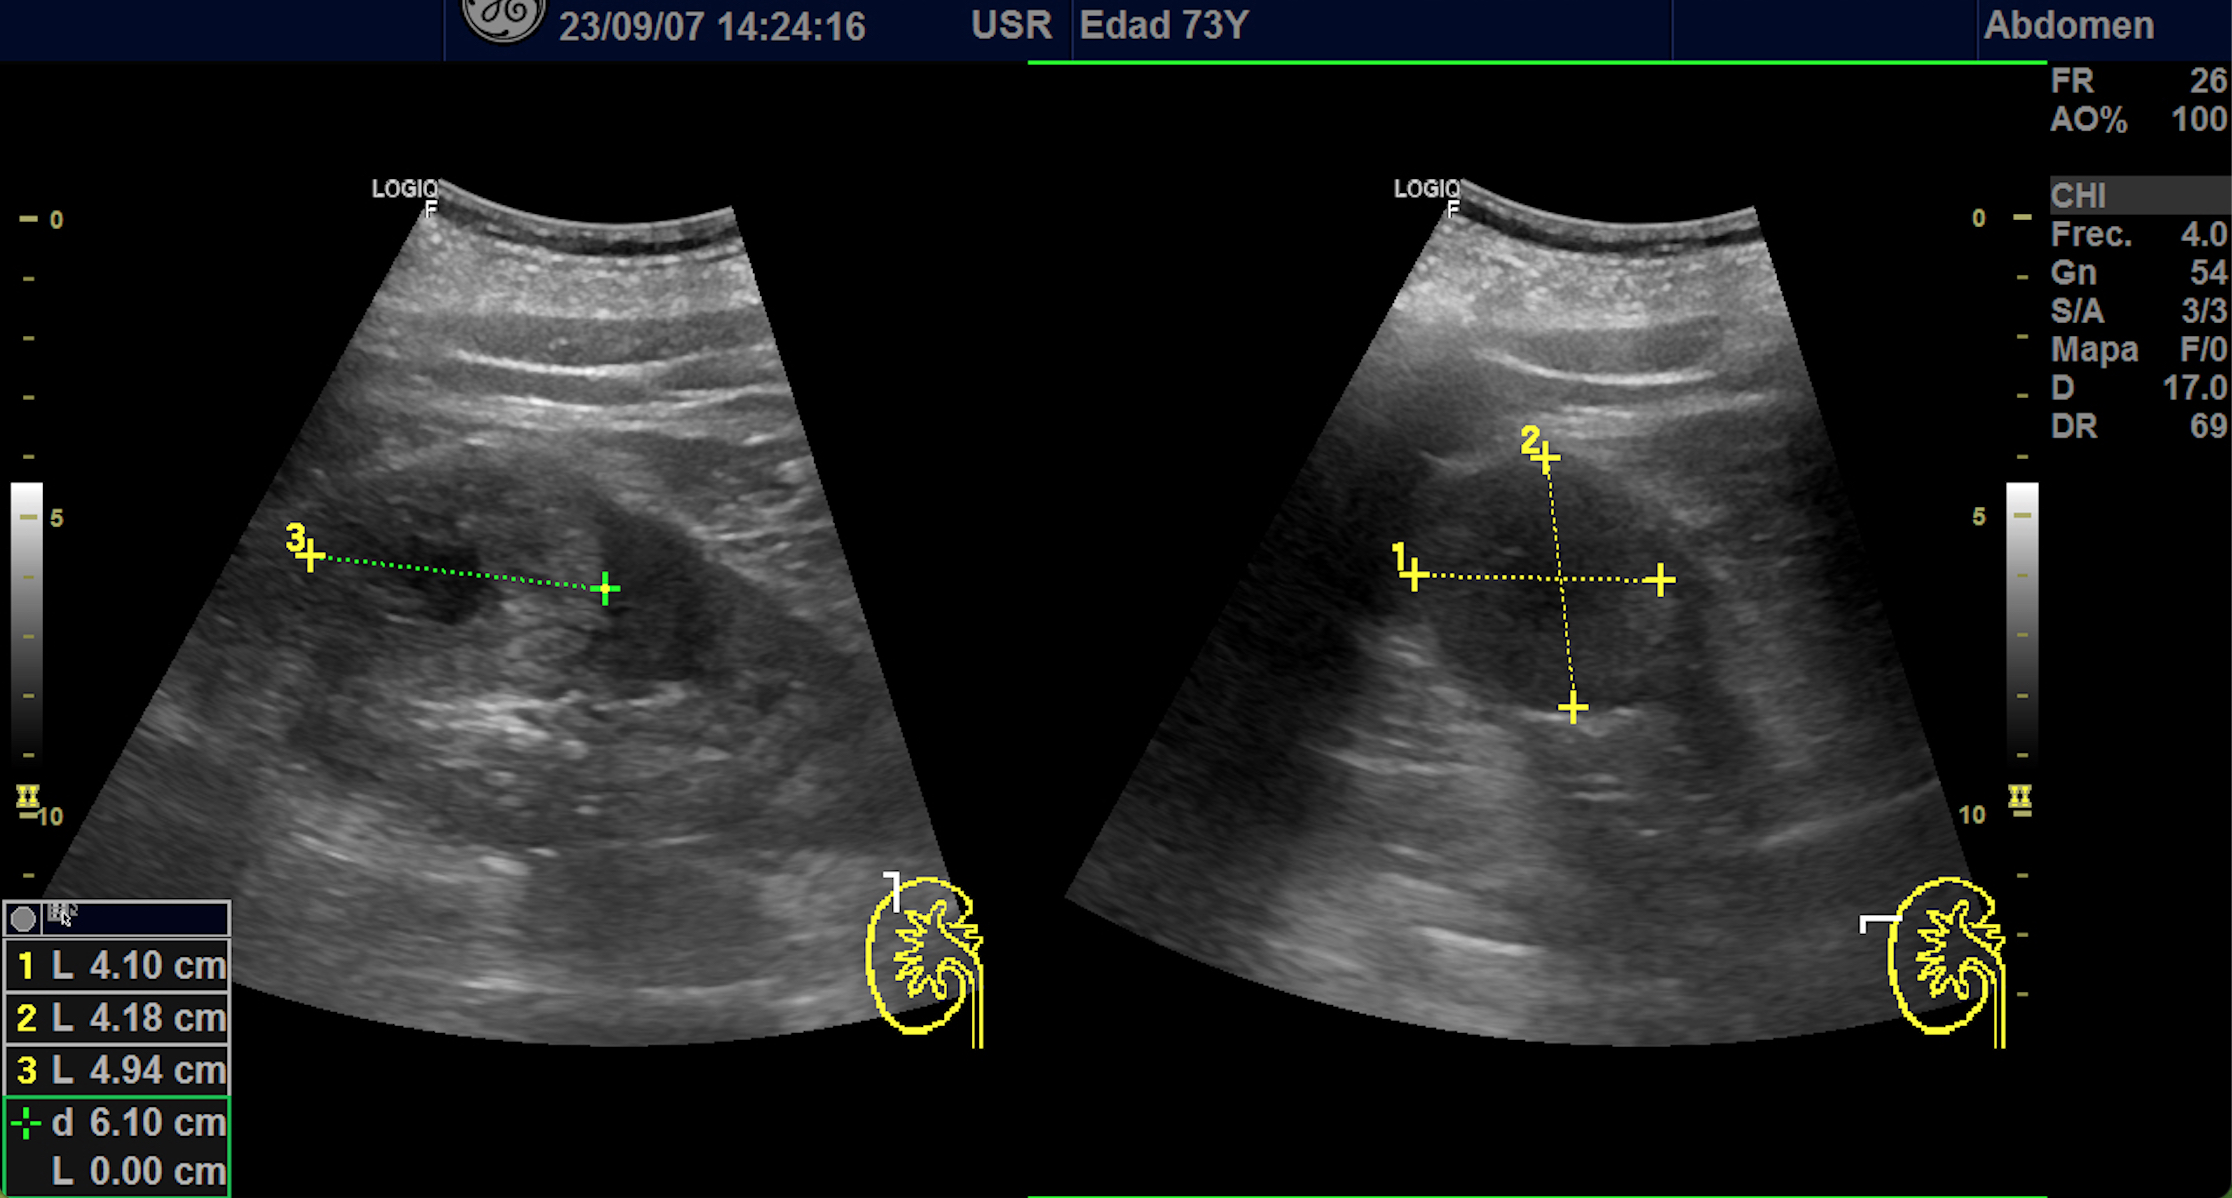

Hallazgos ecográficos

En polo superior de riñón derecho se observa una imagen redondeada, bien delimitada, isoecoica con un área central hipoecoica con vascularización periférica y central de 4,1 x 4,18 x 4,94 cm.